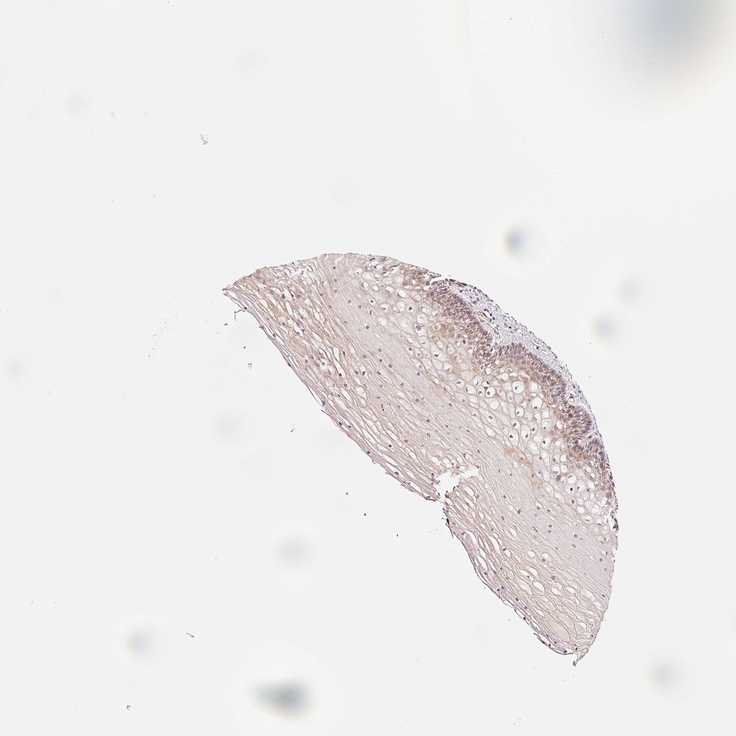

CERVIX - Antibody stainingi

Antibody staining in the annotated cell types in the current human tissue is reported as not detected, low, medium, or high, based on conventional immunohistochemistry profiling in selected tissues. This score is based on the combination of the staining intensity and fraction of stained cells.

Each image is clickable and will lead to virtual microscopy that enables deeper exploration of all samples and also displays staining intensity scores, fraction scores and subcellular localization as well as patient and tissue information for each sample.

Antibody HPA046149Antibody HPA050196Antibody CAB010100

Glandular cells MediumLowHigh

Squamous epithelial cells LowNot detectedMedium